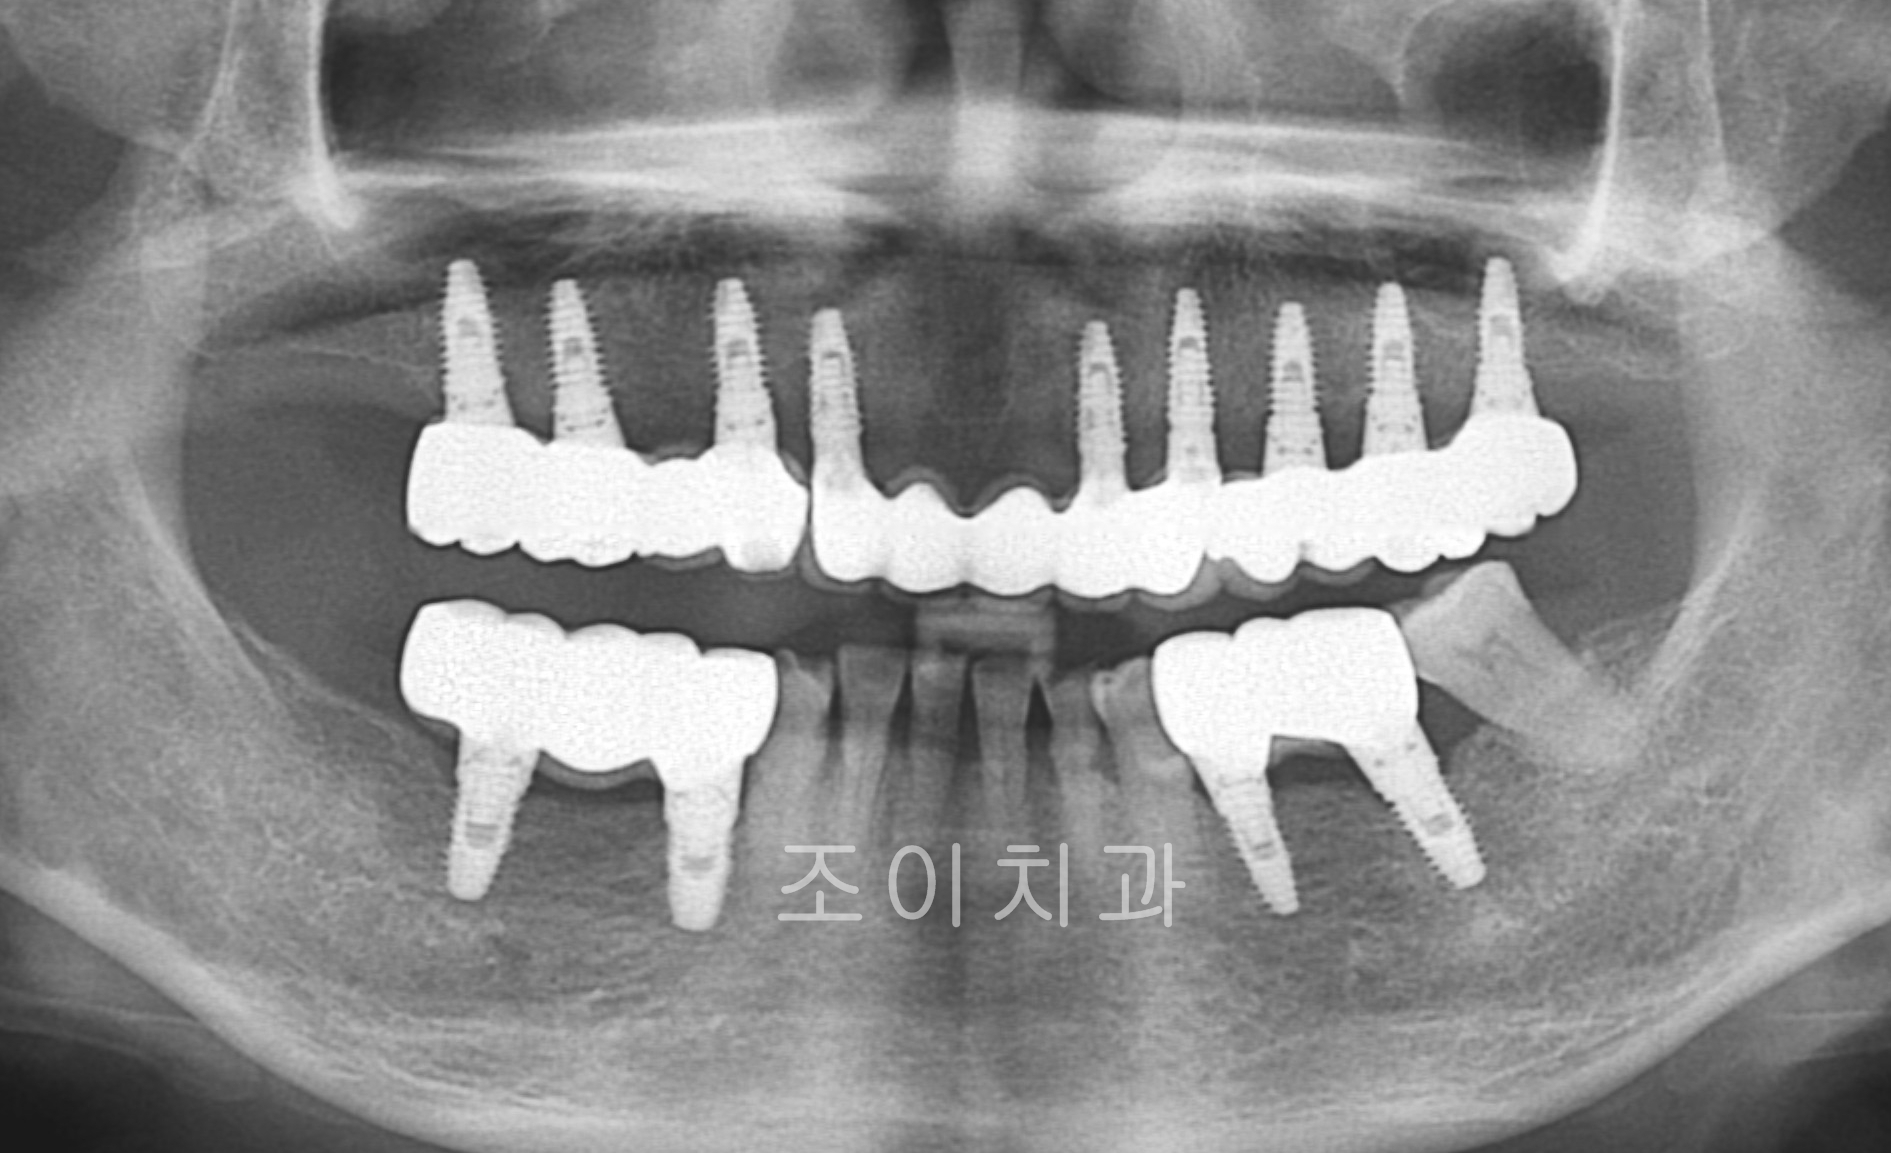

[임플란트] 제목 : 상악 전악 및 하악 구치부

x-ray